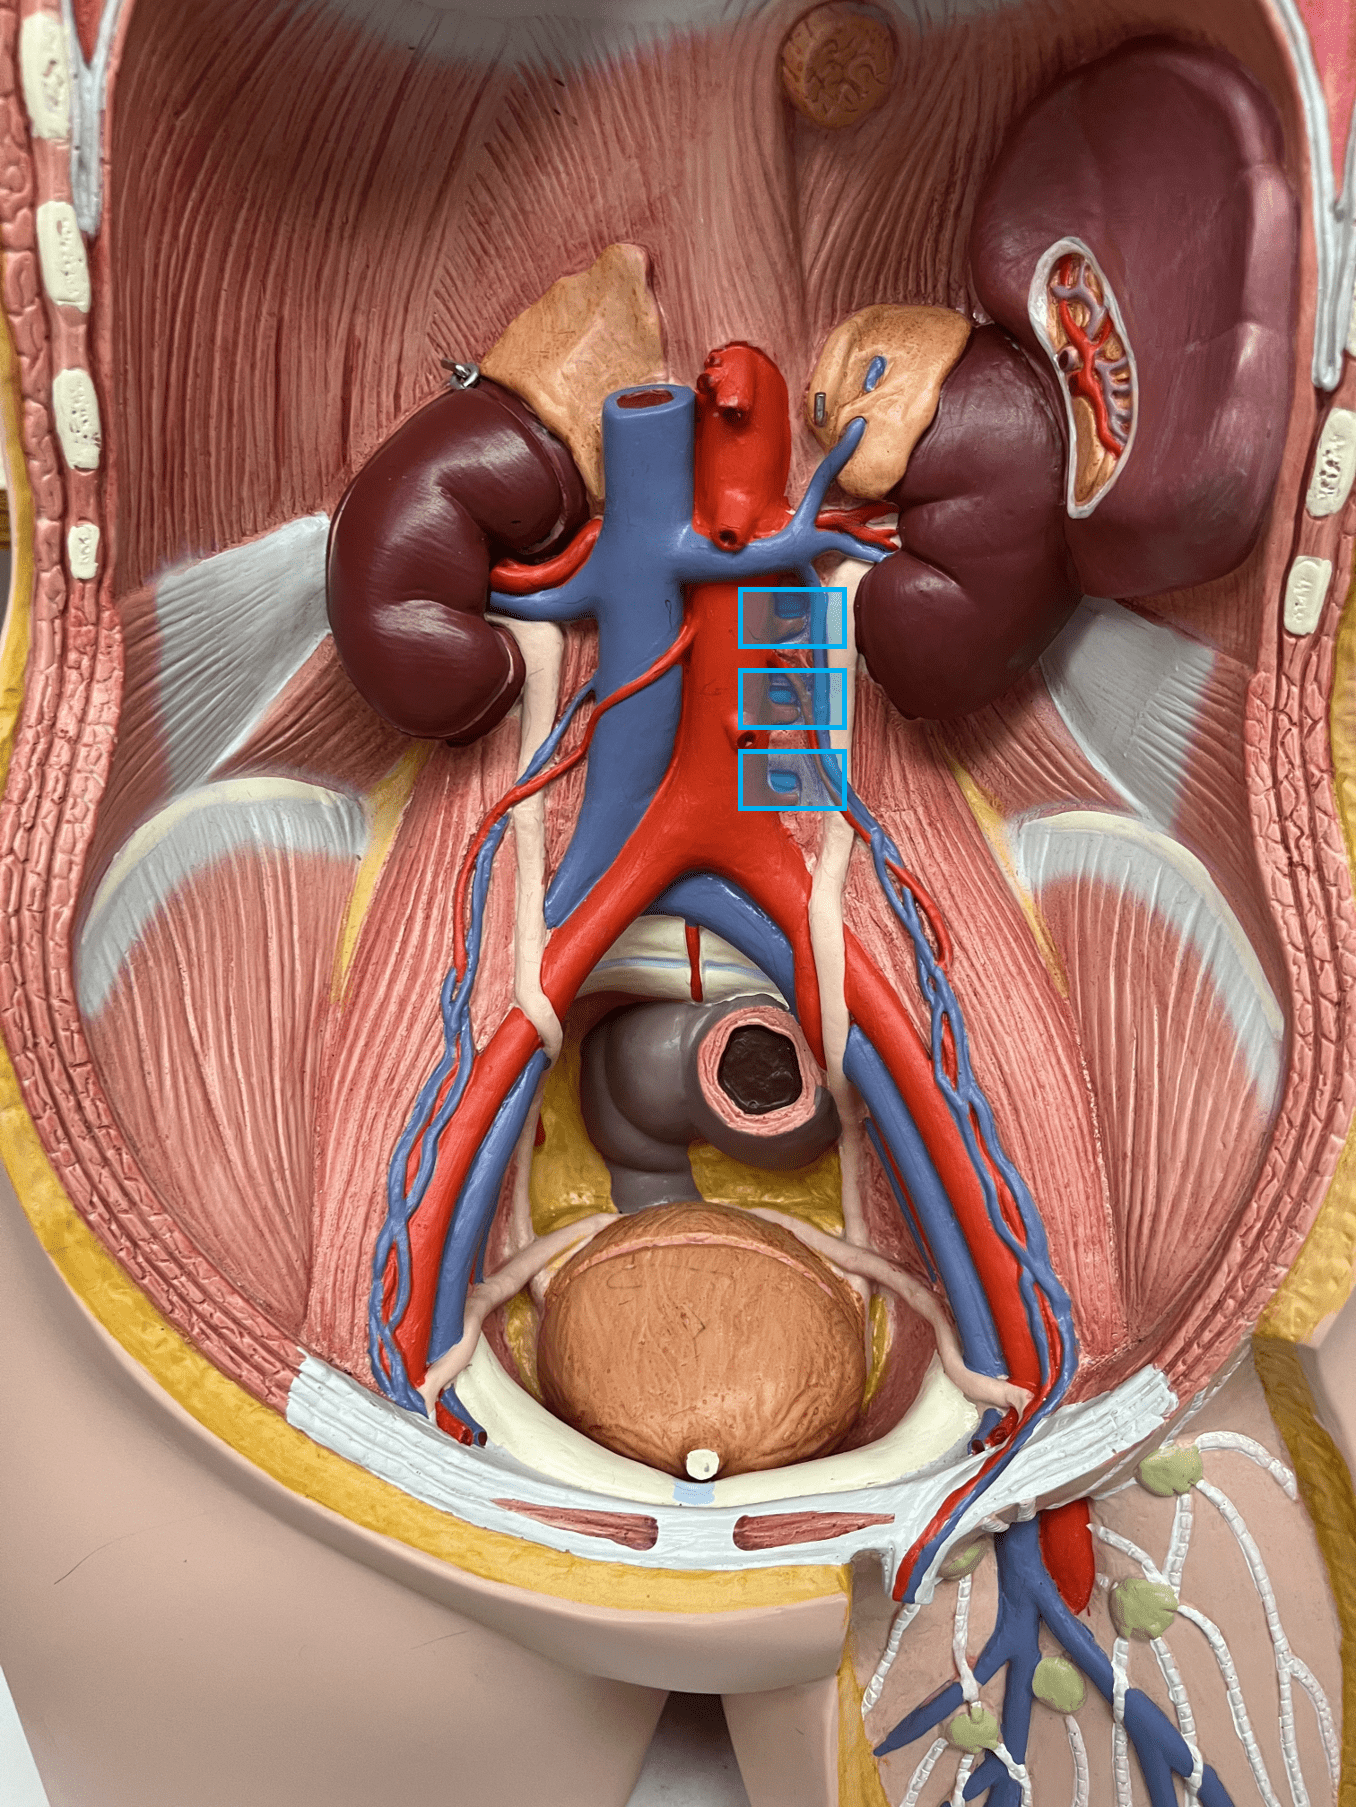

New cards

external elastic membrane

• A thin layer of elastic connective tissue.

• Found between the tunica externa and tunica media.